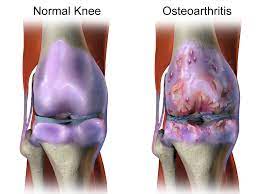

관절염 원인

- 노화: 나이가 들면서 관절에 부담이 가해져서 관절염이 발생할 수 있어요.

- 손상 및 부상: 관절에 손상이나 부상을 입으면 염증이 발생해 관절염이 생길 수 있어요.

- 유전적 요인: 가족 중에 관절염 환자가 있거나, 유전적인 요인으로 인해 관절염이 발생할 수 있어요.

- 자가면역 질환: 루푸스, 레이노드 현상, 류머티즘 관절염 등과 같은 자가면역 질환은 몸의 면역 체계가 관절을 공격하여 관절염을 발생시킬 수 있어요.

- 감염: 세균, 바이러스, 균류 등이 관절에 감염을 일으키면 관절염이 발생할 수 있어요.